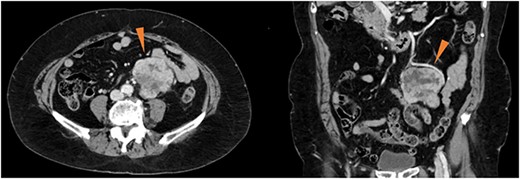

An 82-year-old woman with an abdominal mass was referred to our hospital. She had previously undergone ovarian mucinous cystadenoma with bilateral salpingo-oophorectomy 3 years prior, and had uterine leiomyoma. Abdominal contrast-enhanced computed tomography revealed a well-defined heterogeneously enhanced mass near the left ovarian artery and ureter (Fig. 1). No signs of metastases were observed. The serum tumor marker levels, including cancer antigen 19–9 and carcinoembryonic antigen, were within the reference ranges.

Contrast-enhanced computed tomography showing a well-defined, heterogeneously enhanced mass (red triangles) in the vicinity of the left ovarian artery and left ureter.